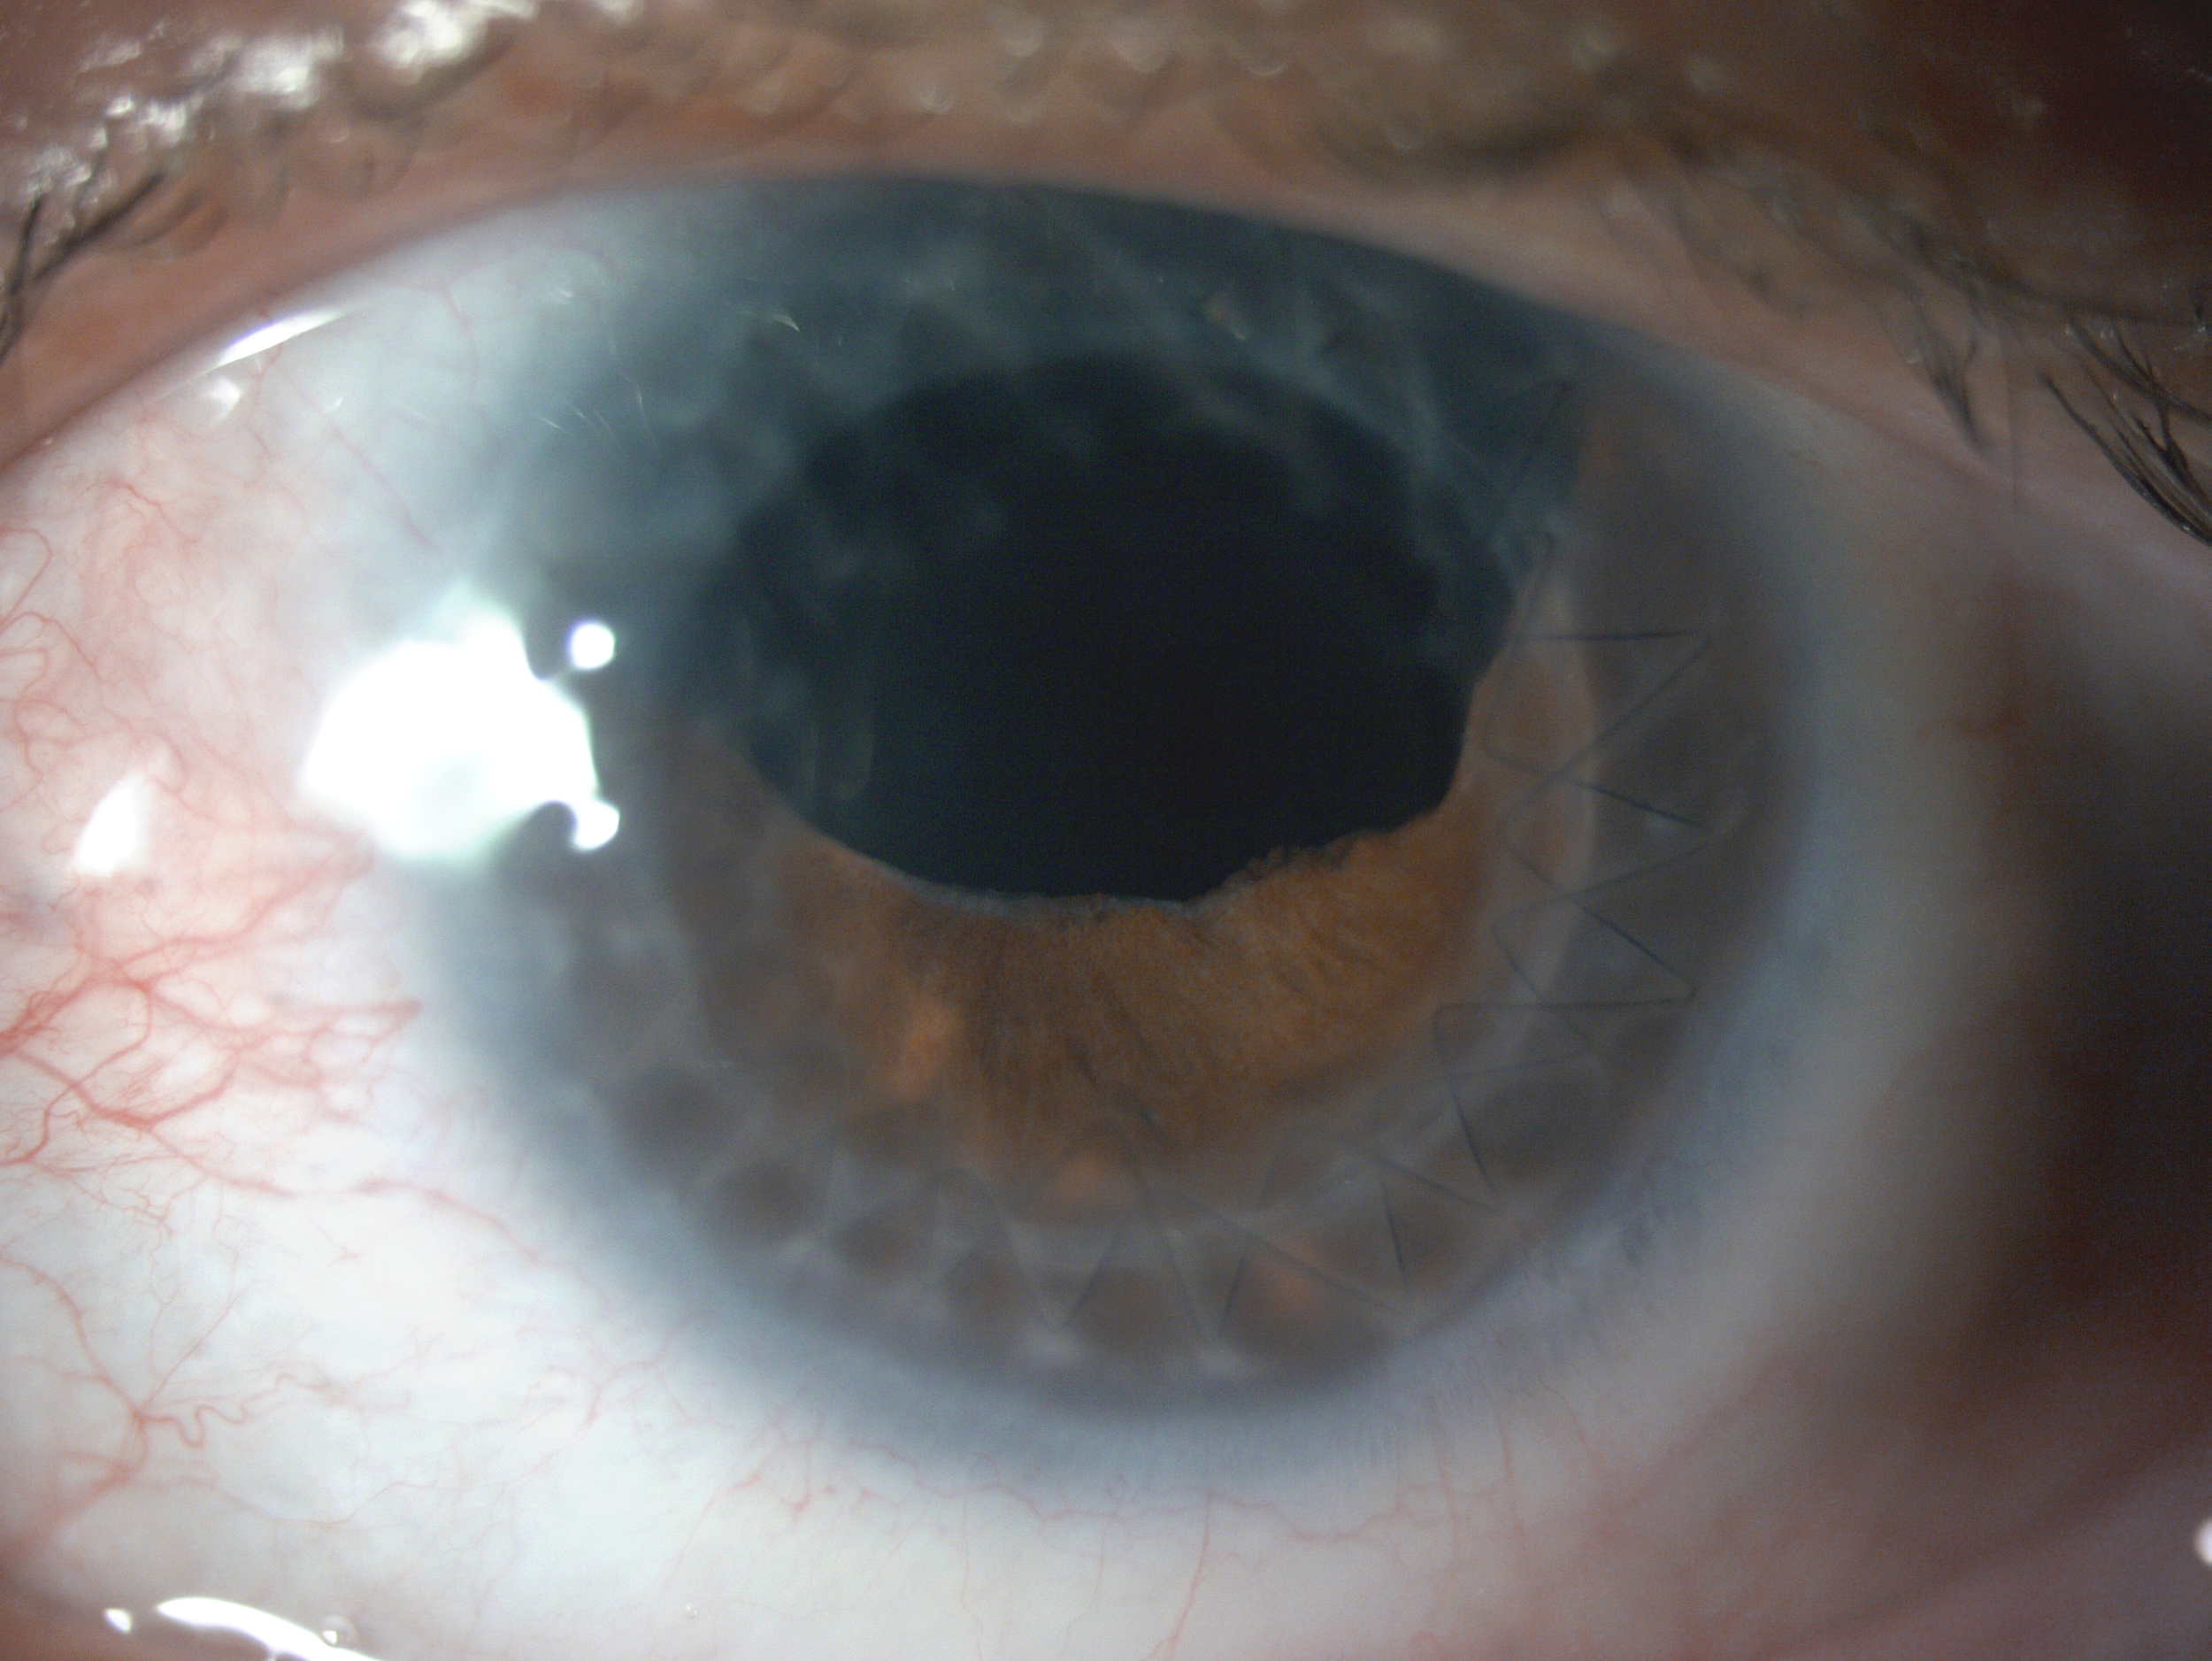

Rather than sitting directly on the eye like a traditional soft lens, scleral lenses only touch the sclera (the white part of the eye) and vault entirely over the cornea (the front of your eye - a clear layer of tissue that covers your iris, pupil and lens). This vault - the space between the contact lens and your cornea - is filled with fluid and creates a new, perfect focusing surface.

By vaulting over the eye with fluid, we are able to manage complicated eye conditions such as astigmatism, keratoconus, corneal transplants, severe dry eye, corneal scarring, LASIK complications and more. These lenses can be life changing.

A scleral lens consultation is the best place to start! Slam dunk cases tend to be those who have high astigmatism, irregular corneas, keratoconus, corneal scarring, corneal transplant, post-lasik, post-RK, severe dry eye, Sjogren’s Syndrome, and Bell’s Palsy.

At a scleral lens consultation, we will first learn and discuss your eye health history, take profilometry and topography scans, and discuss your needs. If you are new to scleral lenses, we will place a “demo” scleral lens on your eye(s) to check the vision potential of your eyes, as well as to see if your eyes feel better if your condition is related to dry eyes. If we determine that you are a candidate and proceed with scleral lenses, our doctor Dr. Seif then orders a unique, custom designed lens and adjusts it until the most optimal vision and fit is achieved.